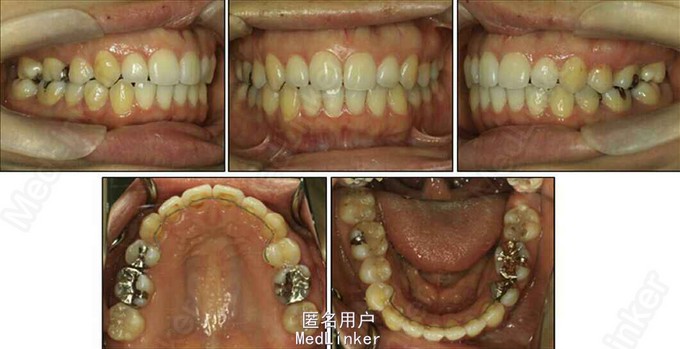

面部:凸面型,上下唇前突,上唇E线前3.5mm,下唇E线前9.5mm,闭唇时口周肌肉紧张。口内检查:双侧尖牙磨牙I类关系,左侧7锁合,覆盖4.5mm,覆合1mm,中线正,上颌拥挤度12.5mm,下颌拥挤度8.2mm。全景片示4个第三磨牙均阻生,怀疑上颌第二磨牙远中面因8阻生有牙根吸收,下颌8近中倾斜阻生更严重,右下6、左下4和5都行了RCT并大面积充填。头影测量示骨性I类,高角,下切牙唇倾。无TMJ症状,只是咀嚼测试时,右侧(非锁合侧)较左侧速度更快且更稳定。

诊断:安氏II类1分类,双颌前突,牙列严重拥挤,左下7锁合,双侧上7牙根吸收,四颗第三磨牙阻生 治疗目标:减少唇的突度及前牙拥挤,扶正4颗阻生的第三磨牙,达到良好的面部美观和功能咬合。 治疗:上颌拔除2颗5和2颗7(不拔4的原因为左上4为正常牙,左上5大面积充填;右上4形态较右上5好。因拔除了坏牙保留了健康牙齿,但是拔5不利于前牙的内收,所以于上后牙56之间植入了支抗钉加强支抗,辅助内收前牙。拔7原因为两颗7远中面均有牙根吸收且有大面积充填),下颌左侧拔除5和7(左下5根管治疗且根尖阴影,拔除左下7原因为严重锁合,改正困难且容易导致上下磨牙的伸长加重II类高角面型),右侧拔除根管治疗且大面积充填后的6;分别竖直4颗近中倾斜阻生的8,整个疗程39个月,四颗8成功的代替6或7。双侧I类尖牙关系,左侧磨牙I类关系,右侧磨牙完全远中关系。唇突度改善,全景片可见达到可接受的牙根平行度,4个8完全萌出直立。以前因为锁合导致的两侧咬合不对称没有了。

用阻生的第三磨牙代替缺损很大的磨牙是保留健康牙齿很有效的方法。患者1年后5个月随访,效果依然稳定。